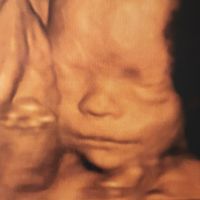

DEPISTAGE DE LA TRISOMIE 21